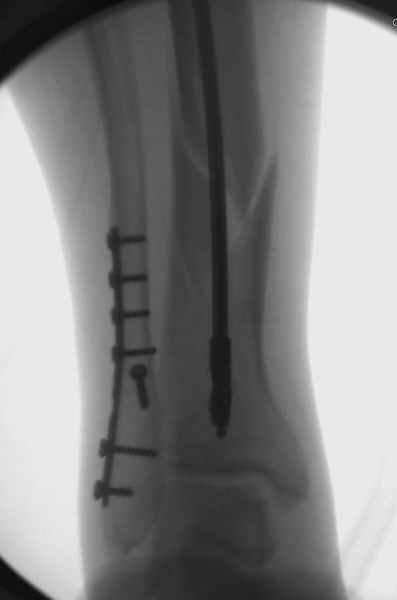

Здесь мы использовали новый Synthes Nail с дополнительными дырками, в проксимальной части 4: по две косых и поперечные (один стандартный а другой динамический), в дистальной части две поперечные, прямая и косая. Вес больного более 120 кг, нагрузку начнем через месяц.